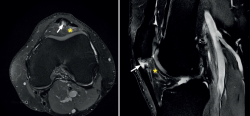

Figure 1. Ultrasound images (linear probe) of the patellar tendon, distal portion. Longitudinal view of the tendon fibres at insertion in the anterior tibial tuberosity (ATT). A: distal insertion of the normal patellar tendon. The arrow shows mild bursitis, and the double arrow indicates the normal size of the tendon; B: distal patellar tendinopathy showing the deep infrapatellar bursa (arrow) containing fluid (hypoechoic image), with increased tendon thickness (double arrow) and a fibrillar pattern showing decreased echogenicity (hypoechoic) secondary to disruption of the collagen bands (asterisk).

Distal PT in the adult (Figure 1) is also found as a complication of Osgood-Schlatter disease. This form of osteochondritis of the anterior tibial tuberosity manifests at prepubertal ages (males: 12-15 years; females: 8-13 years), it is produced by traction of the tendon upon its distal insertion in the distal tuberosity of the tibia, and is characterised by pain in response to palpation of the anterior tibial tuberosity in the physical examination(13). Its appearance has also been described at 12-18 months, before the completion of skeletal maturation(14).